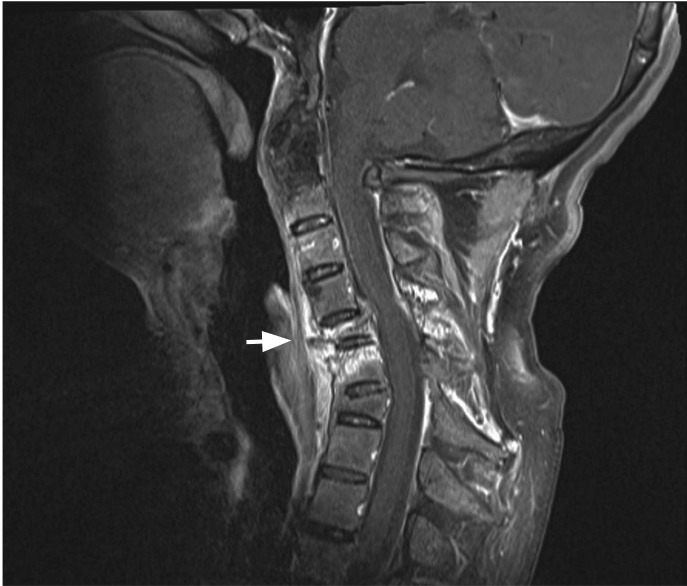

Figure 2

Gadolinium-enhanced fat-suppressed T1-weighted magnetic resonance image shows a recent compression fracture of the C5 vertebral body (arrow) and resultant spinal cord compression, as well as an old compression fracture of C7.

A 51-year-old man with a 22-year history of ankylosing spondylitis who had been treated with nonsteroidal anti-inflammatory drugs and infliximab presented with severe posterior neck pain, which had been aggravated after he fell backwards 3 months earlier. The neurological examination was normal. Plain radiographs showed total ankylosis of the cervical spine and a C5 vertebral body fracture with anterior dislocation of C4 on C5 (Fig. 1). There were numerous thin pieces of foreign material along the spine (Fig. 1). The patient said he had undergone Korean traditional gold thread acupuncture therapy, which had not been effective. Gadolinium-enhanced fat-suppressed T1-weighted magnetic resonance imaging showed a recent compression fracture of the C5 vertebral body and resultant spinal cord compression (Fig. 2), as well as an old compression fracture of C7. For cervical spine fractures in ankylosing spondylitis, conservative treatment with gentle low-weight cervical traction can be performed initially, in the absence of a neurologic deficit. However, secondary neurological deterioration occurs frequently due to the delayed dislocation at the original fracture site, and surgical treatment is generally recommended. On surgical exploration of our patient, the C5 fracture was found to be stable and surgical f ixation was not done. The cervical spine is the most frequent site of acute spinal fracture in ankylosing spondylitis, particularly at C5-6 and C6-7. Since the cervical fractures in ankylosing spondylitis are usually unstable, with a high risk of neurological deficits, our patient was lucky not to have had any significant neurological complications.